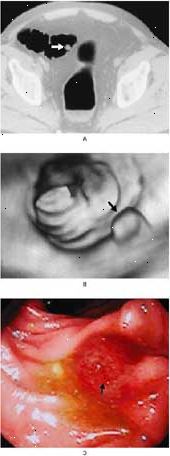

Virtuální kolonoskopie je bezpečná, neinvazivní způsob, jak najít tlustého polypy a jiné abnormality. Nejdůkladnější screening kolorektálního karcinomu zahrnuje lékaře, sledování celého tlustého střeva. Virtuální kolonoskopie umožňuje lékaři zkoumat celou tlustého střeva pro polypů a karcinomů pomocí CT skener a virtuální reality software. O to je méně invazivní než standardní screeningových metod. Konvenční kolonoskopie, například, vyžaduje použití Dlouhodobé sledování trubice, která je zavedena do konečníku a tlustého střeva. A barya klystýr může být velmi nepříjemné procedury. Pokud je virtuální kolonoskopie povzbuzuje více lidí, aby se screening, experti říkají, že by to mohlo zachránit tisíce životů.

CT vytváří detailní snímky z tlustého střeva na počítači. Tyto obrázky umožňují radiolog zobrazit polypy či jiné abnormality. Pokud tam žádné nejsou, nebudete potřebovat další postupy. Pokud lékař zjistí, polypů nebo rakoviny, budete muset mít tradiční kolonoskopii. Lékař pak může odstranit tkáň, tzv. biopsii, a studovat pod mikroskopem.